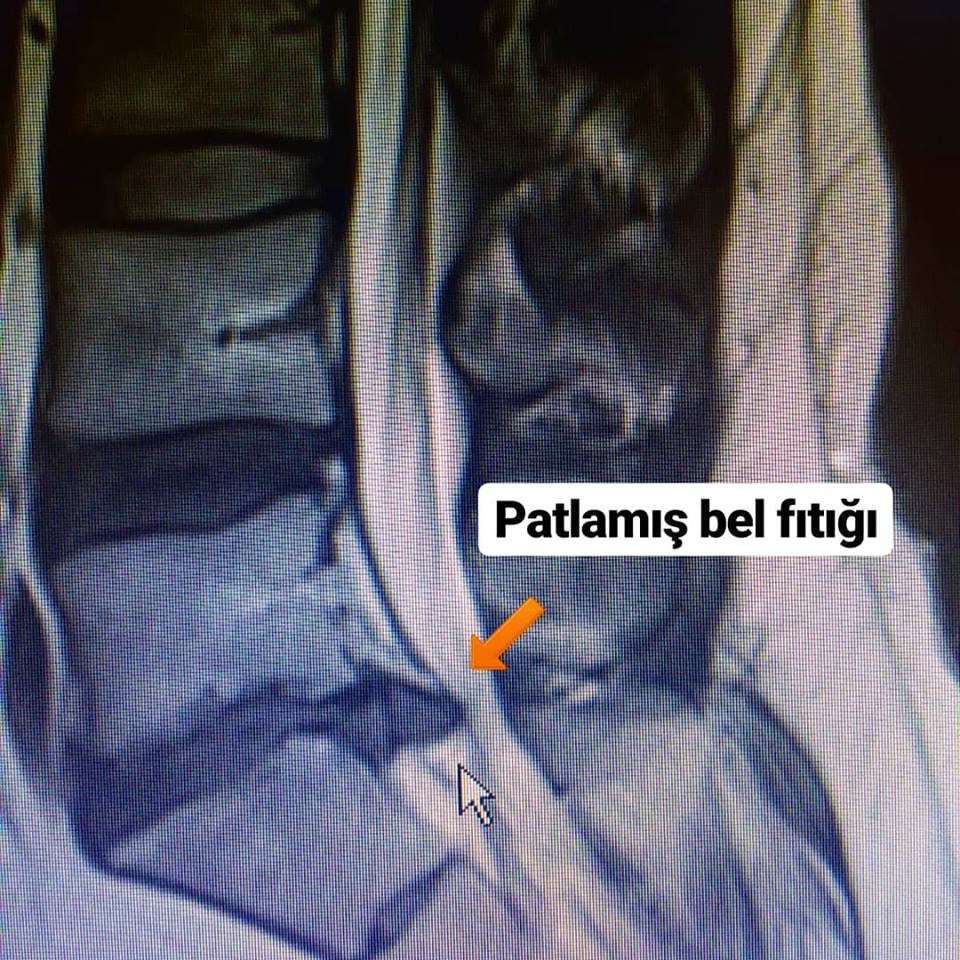

Bel fıtığı patlaması, bel bölgesinde olan omurlar arasındaki diskin dışında bulunan sert tabakanın yırtılmasıyla oluşur. Tabakanın yırtılmasıyla diskin içinde bulunan yumuşak madde dışarıya çıkarak, omuriliğe ya da sinir köklerine baskı yapar ve dolayısıyla ağrıya beden olur. Ağrı belle birlikte bacaklara yayılım gösterir.

Bu durum MİKROCERRAHİ ile tedavi gerektirir.